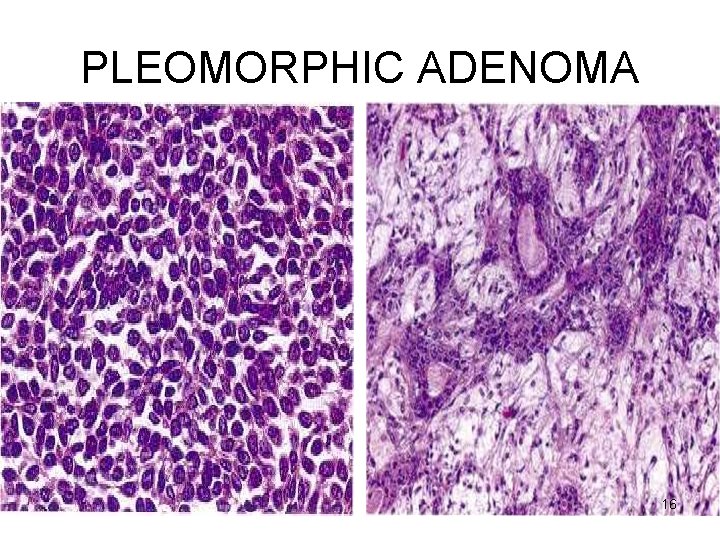

PLEOMORPHIC ADENOMA Microscopy • HETEROGENITY ! → PLEOMORPHIC • EPITHELIAL : epithelial & myoepithelial cells arranged in ducts, acini, irregular tubules, strands, sheets NO DYSPLASIA • MESENCHYMAL : myxoid, hyaline, chondroid, osseous 14